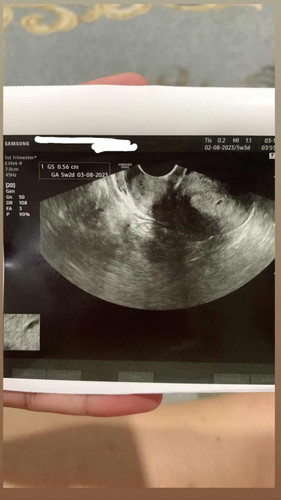

Hai mommies ! Sy nak tanya.. Harini, 8/12 sy dah lewat period 9 hari.. Hari2 sy buat test upt still naik double line samar2.. Sy tak dpt lg double line yg betul2 terang.. Minggu lepas sy ke klinik buat scan dan doc kata mybe kantung.. Klu mommies tgok gmbar tu, ada rupa kantung ke ? 😅 Kecikk betull saiznya 😅😅 #firstbaby #pleasehelp #bantusharing